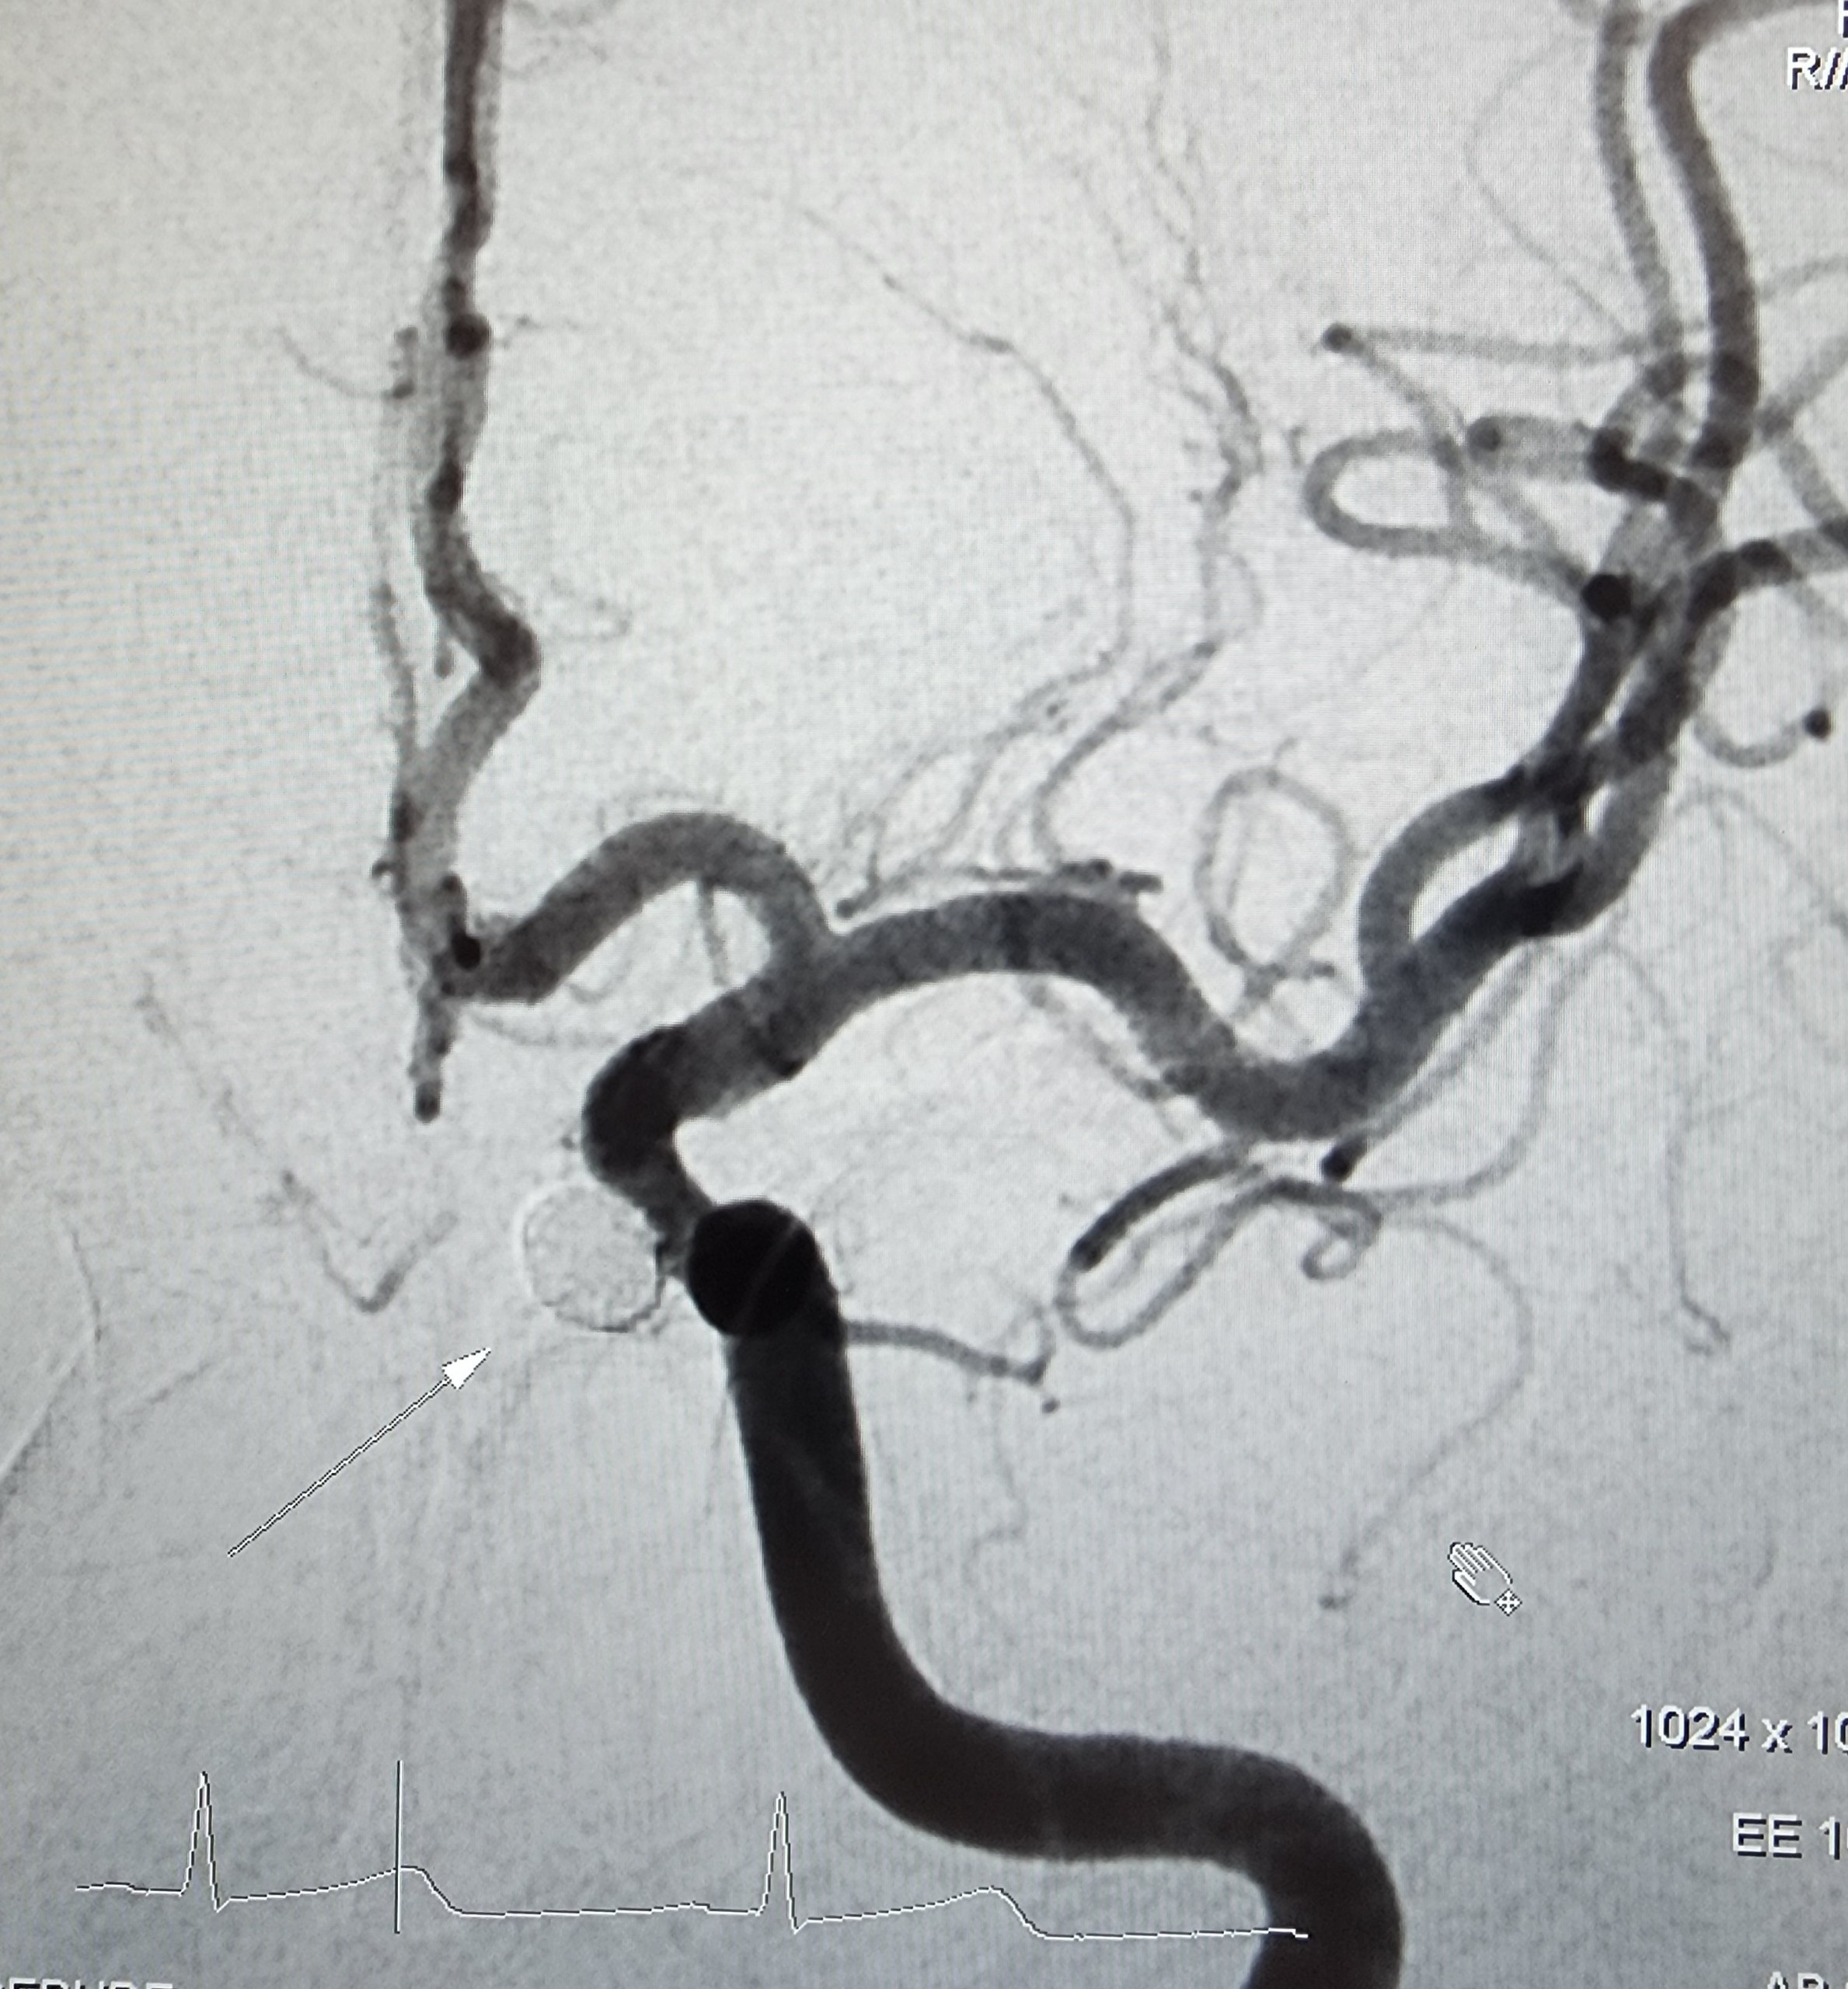

Hình ảnh chụp cộng hưởng từ túi phình động mạch cảnh (bên trái) và túi phình tắc hoàn toàn sau can thiệp (bên phải). |

BS.CKII Thi Văn Gừng - Trưởng Đơn vị Can thiệp mạch, Trung tâm Chẩn đoán Hình ảnh và Điện quang Can thiệp, Bệnh viện Đa khoa Tâm Anh TP.HCM - cho biết, vị trí túi phình của bệnh nhân nằm khá sâu, khó tiếp cận bằng phẫu thuật hở. Do đó, can thiệp nội mạch là phương pháp ưu tiên lựa chọn vì ít xâm lấn và đảm bảo hiệu quả điều trị.

Quá trình can thiệp kéo dài một giờ. Các bác sĩ luồn ống thông nhỏ từ động mạch đùi phải, đi theo mạch máu lên não. Sau đó, bác sĩ cẩn thận tiếp cận túi phình, sử dụng các cuộn kim loại đặc biệt (coil) để bít tắc hoàn toàn. Kỹ thuật này đòi hỏi kinh nghiệm dày dạn của bác sĩ vì có thể gây nguy hiểm như lồi coil hay trôi coil ra khỏi túi phình gây tắc nghẽn mạch máu não khác.